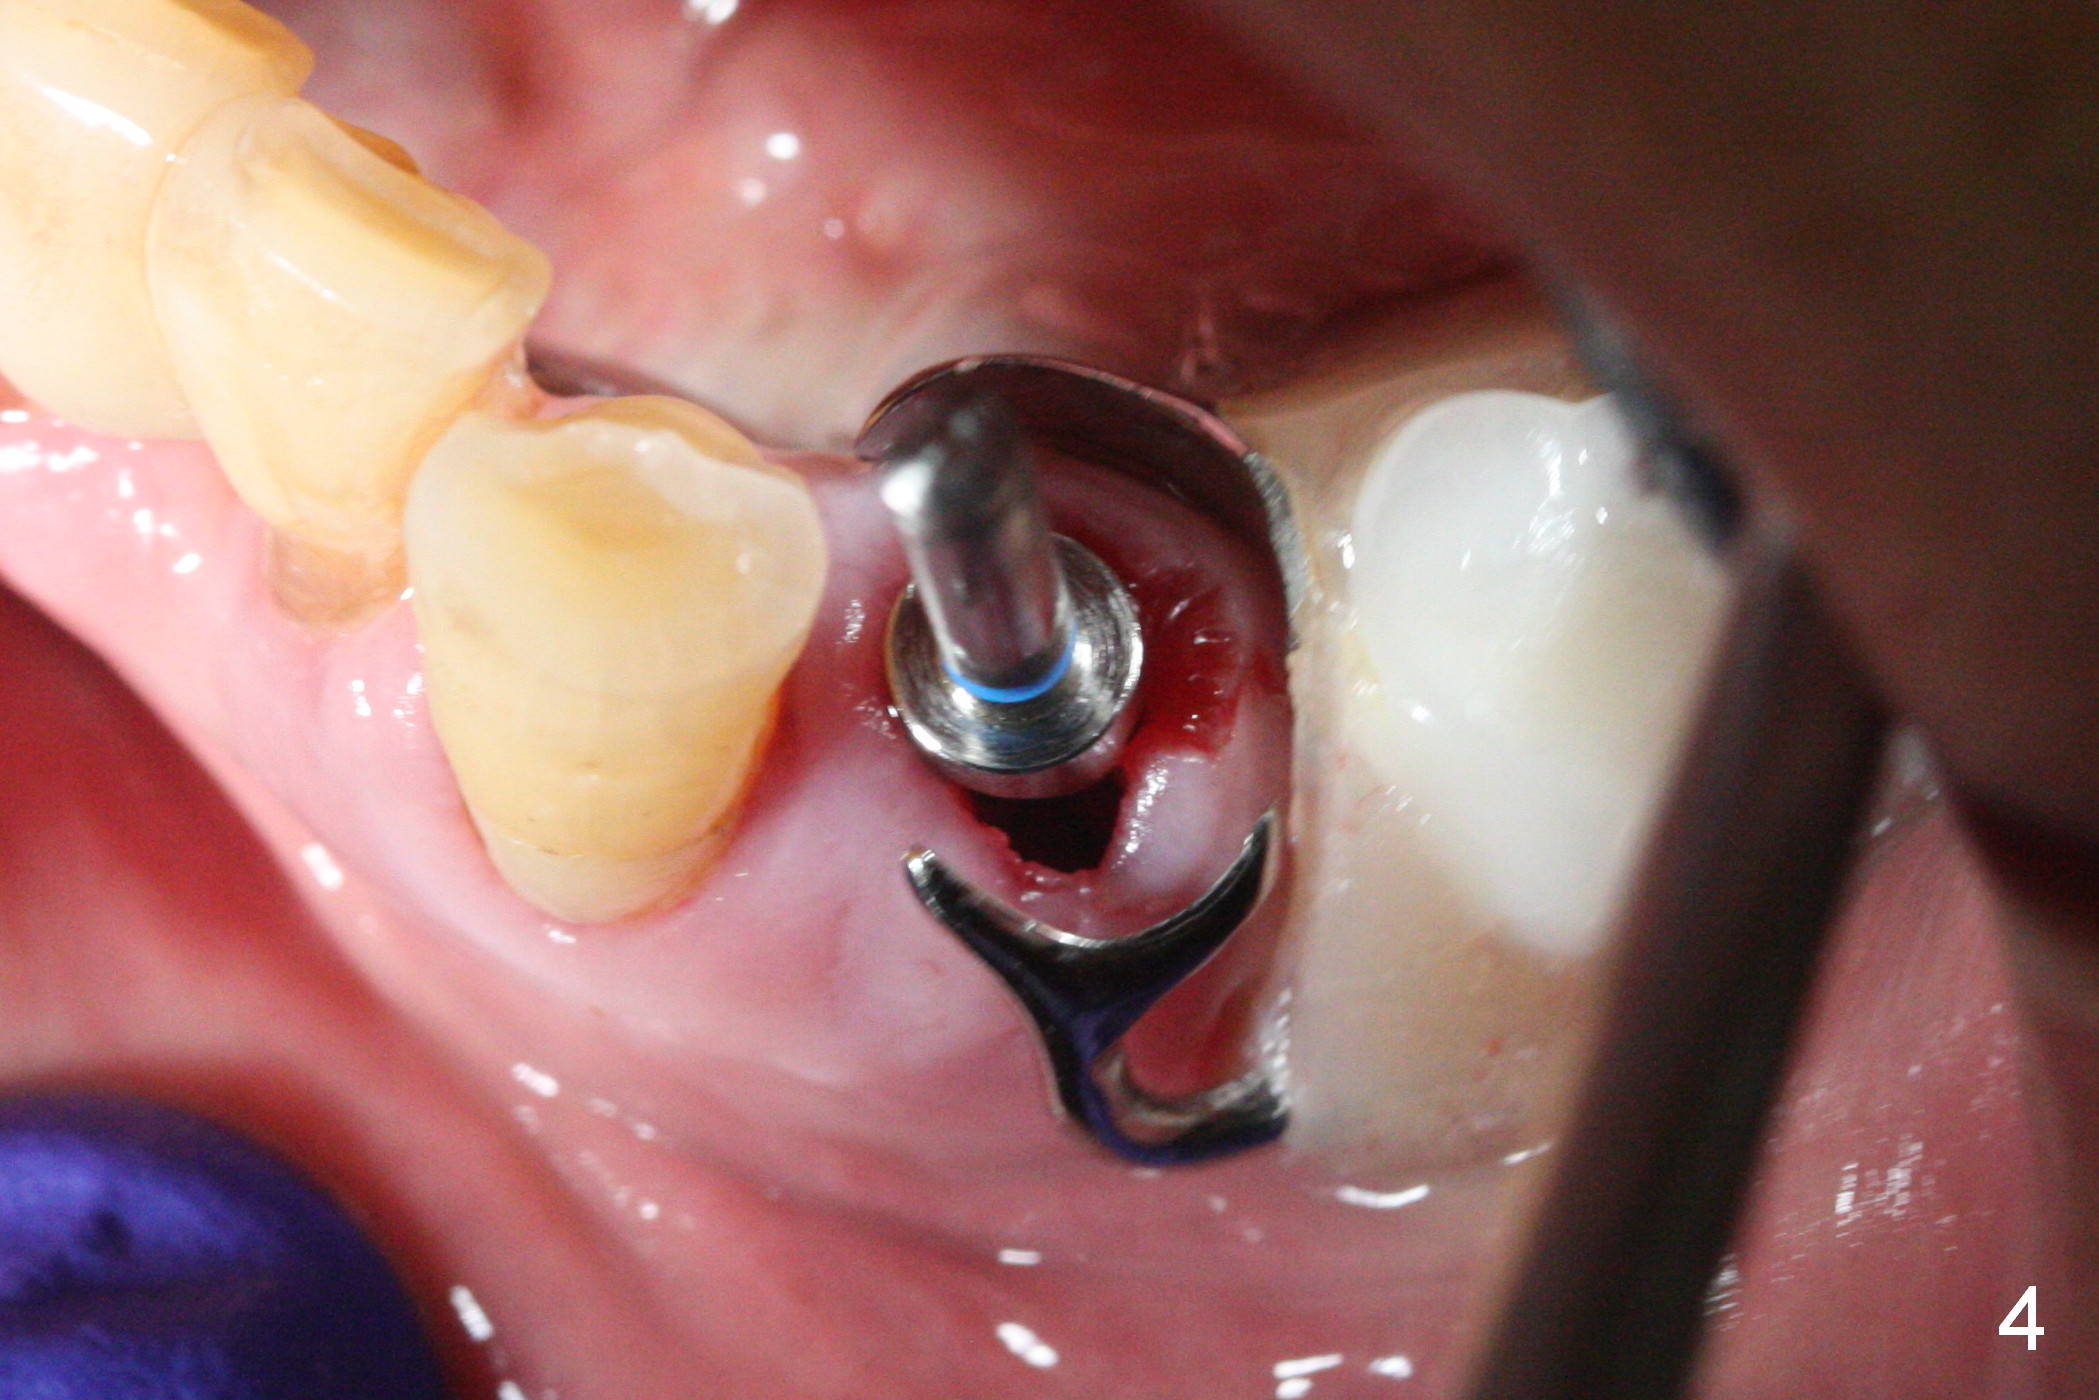

A 72-year-old man presents to clinic for implants because of pain associated with wearing the lower partial. The teeth #21, 24, 25 and 31 seem to be non-salvageable and are going to be replaced by implants so that the lower RPD can be reused (Fig.1). The edentulous ridge is atrophic (Fig.9 *). The upper complete denture appears to be functional. Since the tooth #21 is symptomatic (Fig.2) and the patient has chronic TMJ dislocation, the affected tooth is extracted first (Without antibiotic socket treatment) for immediate implant (Fig.3 (1.5 mm drill (placed more lingually)). The lower RPD is used as a surgical guide (Fig.4 (3 mm drill in place)). When a 3.8x16 mm implant is placed with bone graft (Fig.5 *), the underlying neurovascular bundle is undetected. A small field of panoramic X-ray is retaken; it seems that there is enough clearance from the Mental Foramen (Fig.2,6,7 (red dashed line)) and the Incisive Canal (pink dashed line). The implant is then placed 2 mm more apically (Fig.7) to reduce the chance of periimplantitis since the buccal plate is lost. A 5.5x5(5) mm abutment is placed (Fig.5) with more graft. The access of the abutment is left open so that a part of periodontal dressing is inserted for additional retention (Fig.8,9). The RPD is placed back for adaptation of the dressing. The patient is advised not to wear the RPD postop to reduce micromovement.